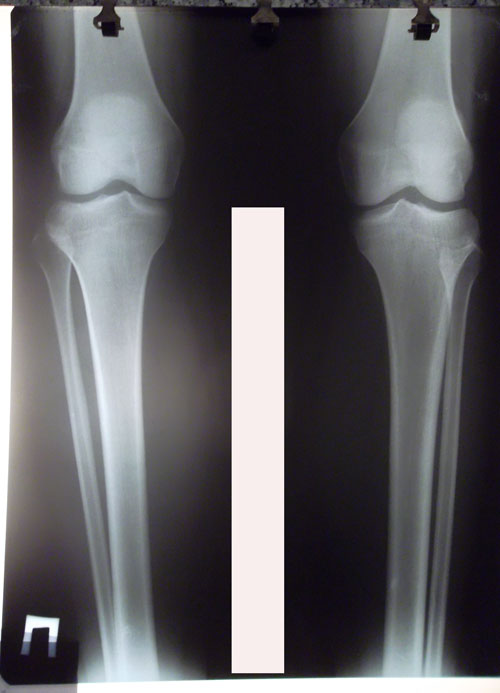

Дата операции 04.04.2016г.

Дата снятия аппаратов 22.06.2016г.

Срок лечения 77 дней.